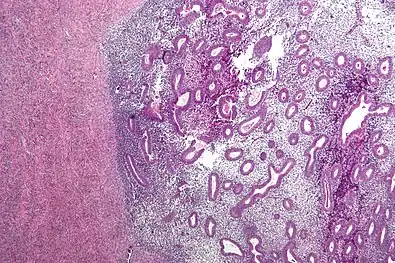

Histopathology

For a histopathological diagnosis, at least two of the following three criteria should be present:[110]

Immunohistochemistry has been found to be useful in diagnosing endometriosis as stromal cells have a peculiar surface antigen, CD10, thus allowing the pathologist go straight to a staining area and confirm the presence of stromal cells and sometimes glandular tissue is identified that was missed on routine H&E staining.[111]